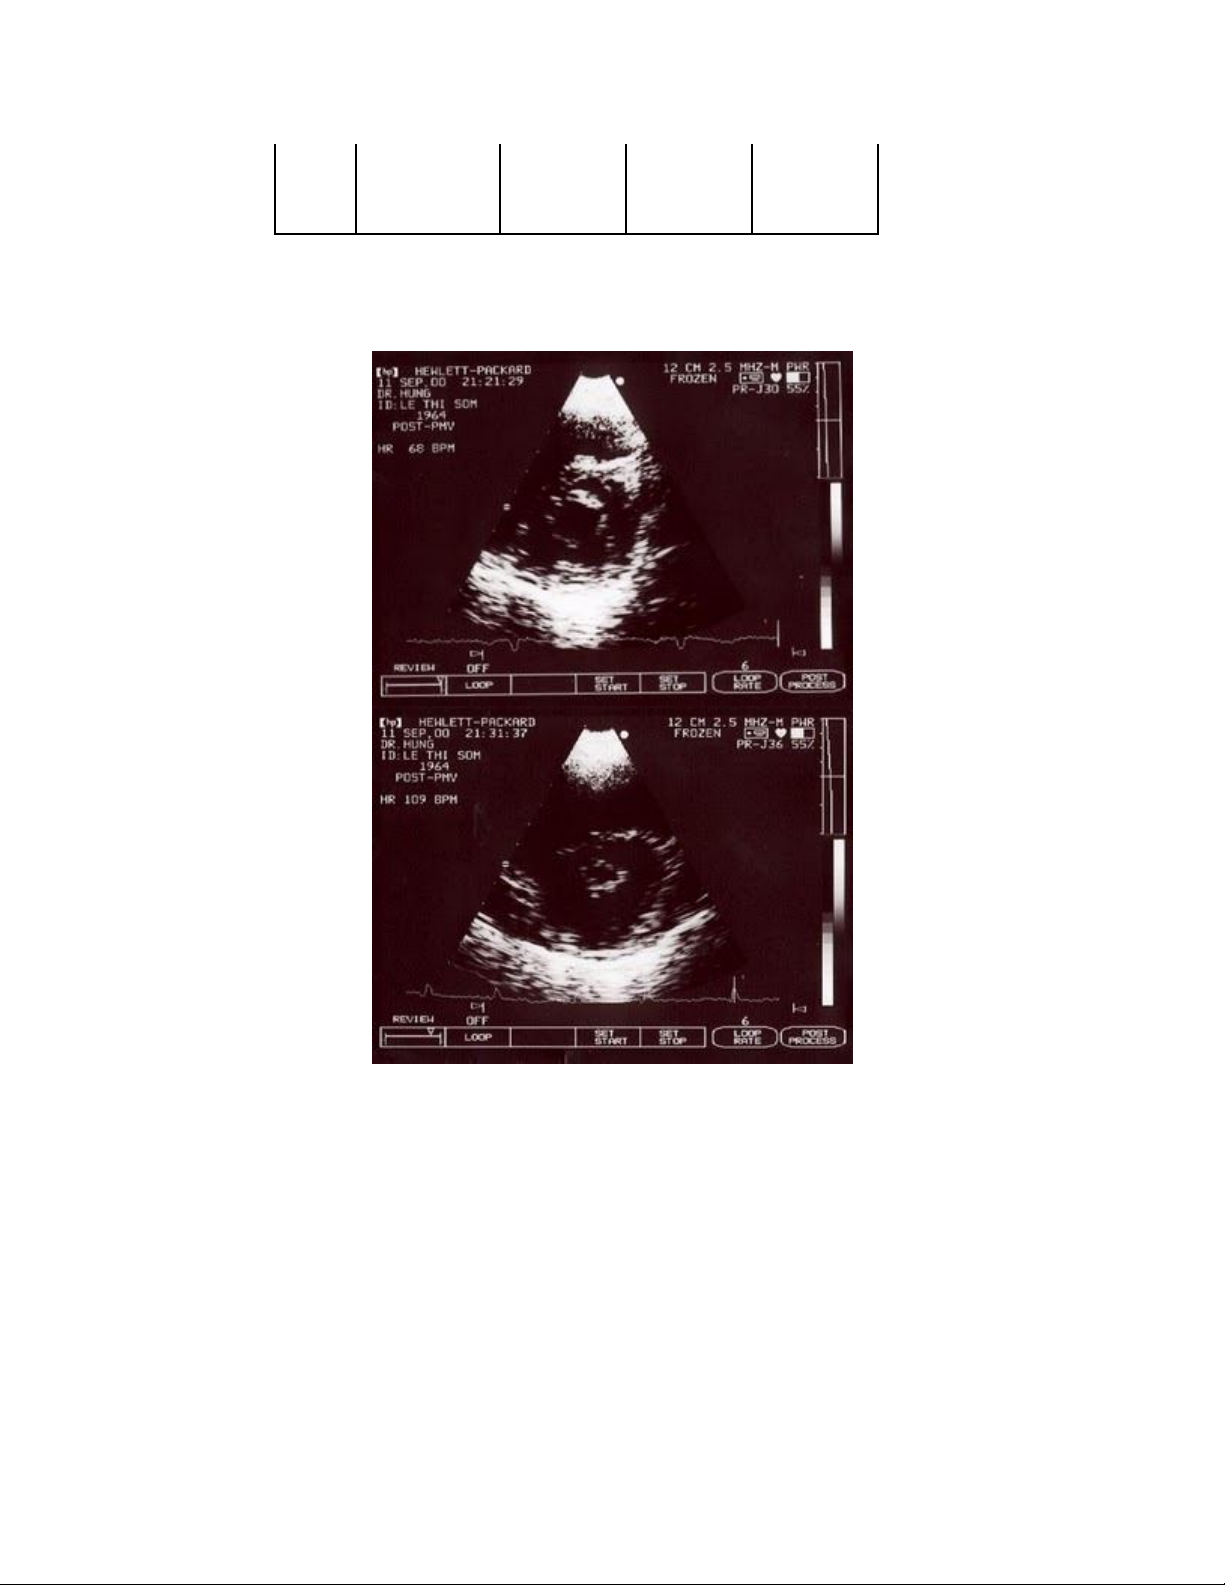

Hình 12-6. Lỗ van hai lá trước và sau nong bằng bóng.

7. Diện tích lỗ van hai lá sau nong: nên được đánh giá bằng cách đo trực tiếp

trên siêu âm 2D. Diện tích lỗ van hai lá tính bằng phương pháp PHT thường ít tin

cậy trong vòng 24-48 giờ sau nong (do huyết động thay đổi nhanh chóng).